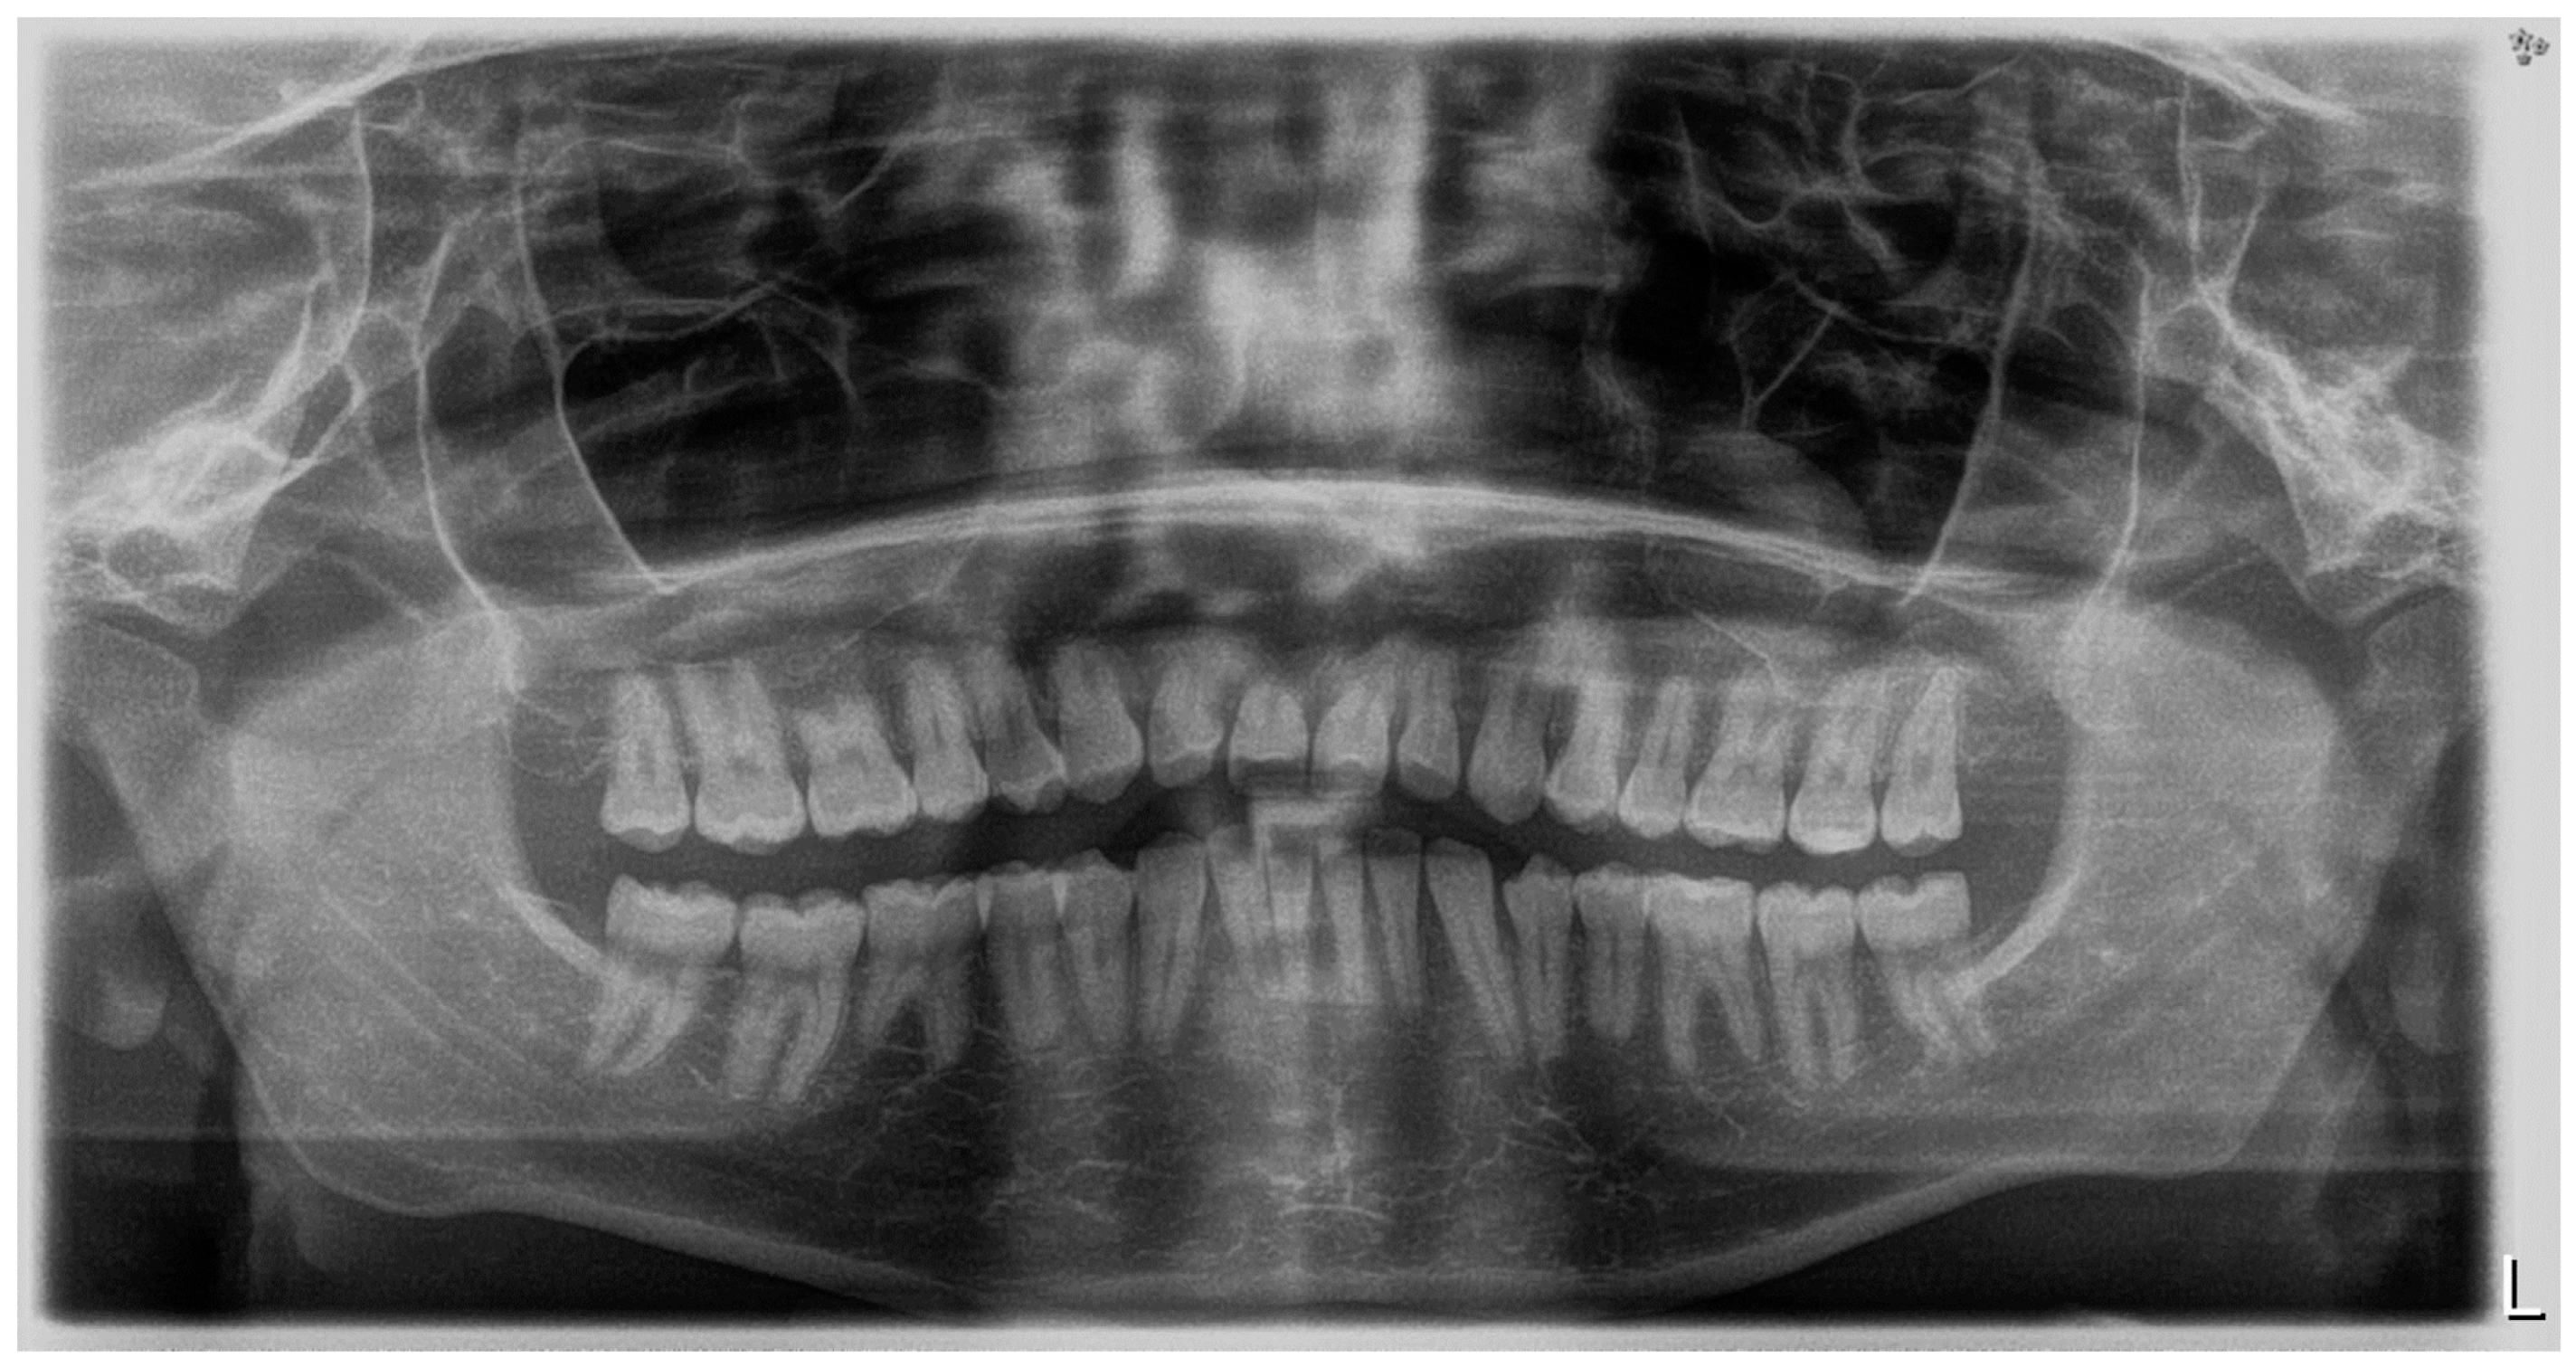

2.1. Diagnosis and Aetiology

2.3. Treatment Progress

3. Results